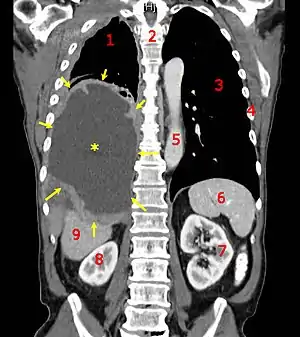

A coronal CT scan showing a malignant mesothelioma Legend: → tumor ←, ✱ central pleural effusion, 1 & 3 lungs, 2 spine, 4 ribs, 5 aorta, 6 spleen, 7 & 8 kidneys, 9 liver | |